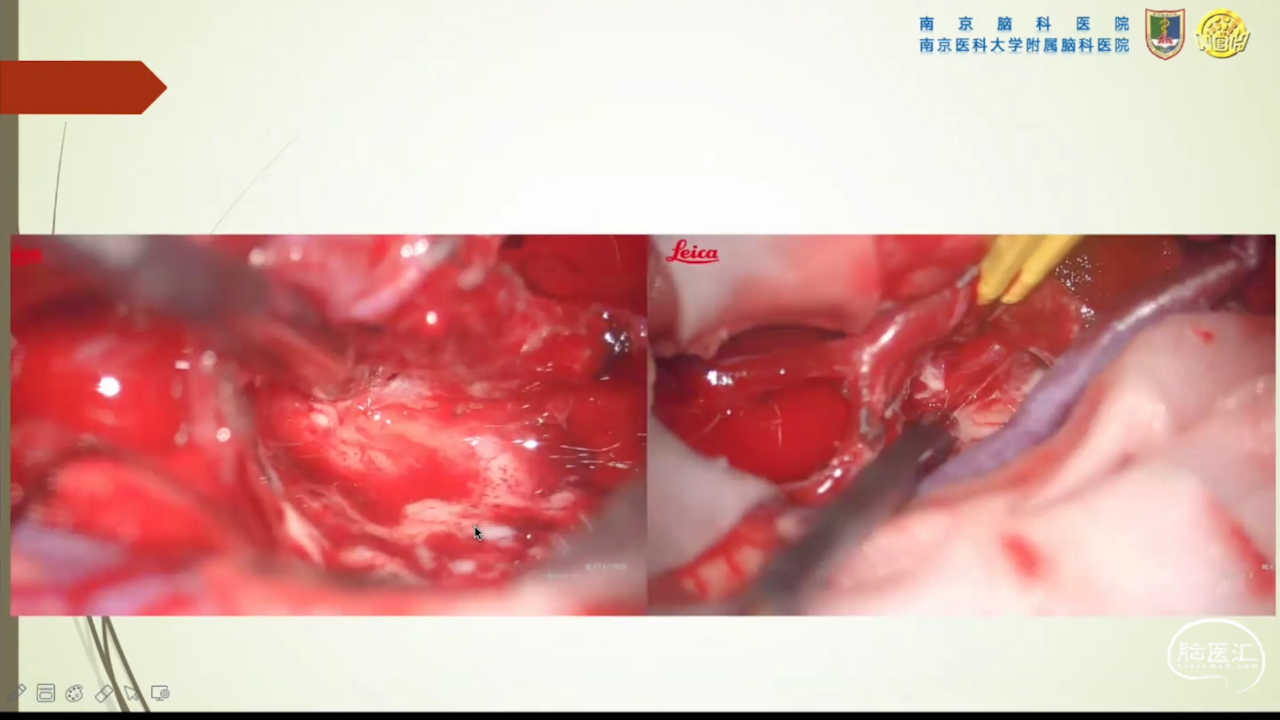

胶质瘤是发病率最高的颅内肿瘤(约占44.69%),岛叶是神经胶质瘤的好发部位,大约有25%的低级别胶质瘤及10%的高级别胶质瘤发生在岛叶,大多数岛叶胶质瘤为低级别胶质瘤。岛叶在调节内脏感觉运动、控制心血管交感活性、传入躯体感觉中均起重要作用。它也参与了痛觉的传递、运动规划、自主性吞咽、味觉、听觉、前庭功能、情绪、认知能力和语言能力。因为岛叶解剖结构复杂,并覆盖有高级语言皮层、白质束及重要的血管结构,故岛叶部位的手术难度极大。

会议内容截图